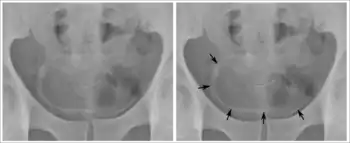

Investigations performed usually include collecting a sample of urine for an inspection for malignant cells under a microscope, called cytology, as well as medical imaging by a CT urogram or ultrasound.[29] If a concerning lesion is seen, a flexible camera may be inserted into the bladder, called cystoscopy, in order to view the lesion and take a biopsy, and a CT scan will be performed of other body parts (a CT scan of the chest, abdomen and pelvis) to look for additional metastatic lesions.[29]

Some forms of medical imaging exist to visualise the bladder. A bladder ultrasound may be conducted to view how much urine is within the bladder, indicating urinary retention. A urinary tract ultrasound, conducted by a more trained operator, may be conducted to view whether there are stones, tumours or sites of obstruction within the bladder and urinary tract. A CT scan may also be ordered.